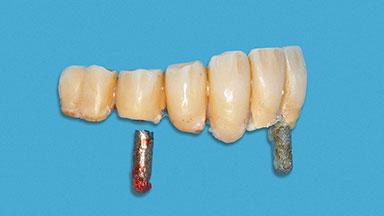

A 93-year-old female patient presented in September 2010 with an enlarged swelling on the lingual side of her lower incisors. At the time, she was essentially healthy, except for reduced vision due to bilateral age-related macular degeneration. She had been a heavy smoker (about 30 cigarettes a day) for the past 20 years after becoming a widow. The patient lived at home by herself, with full-time domestic support. An extraoral examination revealed nothing adverse. Intraoral plaque control was anything but ideal, and a soft-tissue tumescence was visible around the lingual aspect of 41–42. Because the nature of the lesion was not clear, a biopsy was carried out that revealed the inflammatory nature of the lesion. The panoramic radiograph showed six irregularly distributed mandibular implants supporting a full-arch prosthesis, with various degrees of interproximal peri-implant resorption. The periapical radiograph revealed interproximal bone resorption mesially and distally to implant 41.

# of Implants 2

Type of Implants One-Piece

Prosthesis Type FDP